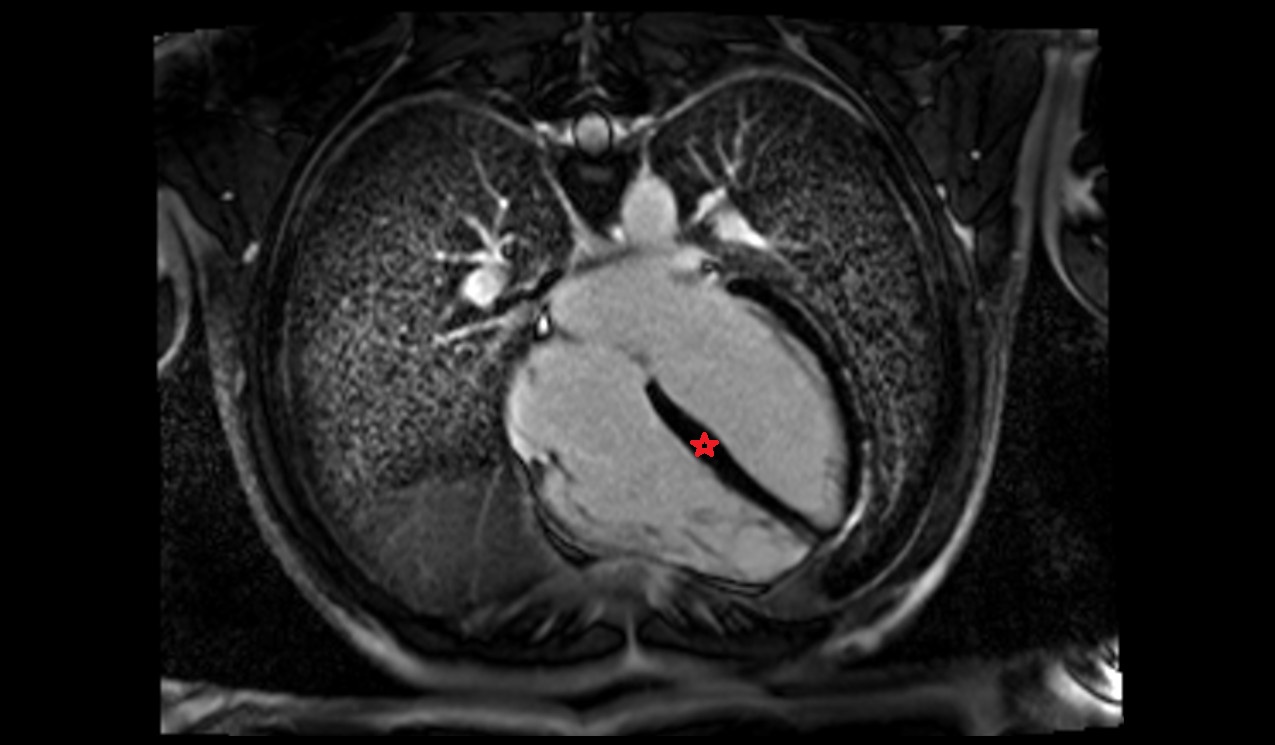

- Pericardium

- Heart

- Left ventricle

- Right ventricle

- Interventricular Septum

- Left atrioventricular valve (mitral or bicuspid valve)

- Right atrioventricular valve (tricuspid valve)